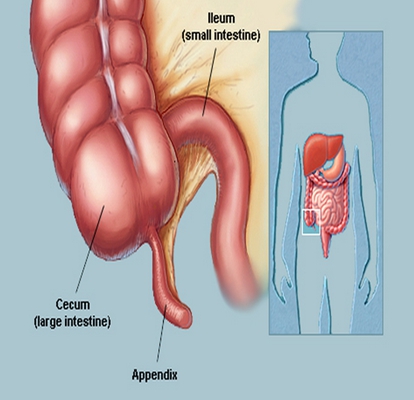

盲腸的位置 (50)

盲腸的位置 (6)

盲腸的位置 (7)

盲腸的位置 (8)

盲腸的位置 (9)

盲腸的位置 (46)

盲腸的位置 (47)

盲腸的位置 (48)

盲腸的位置 (49)

盲腸的位置 (5)

盲腸的位置 (42)

盲腸的位置 (43)

盲腸的位置 (44)

盲腸的位置 (45)

盲腸的位置 (41)

盲腸的位置 (40)

盲腸的位置 (30)

盲腸的位置 (31)

盲腸的位置 (32)

盲腸的位置 (33)

A:盲腸炎症狀最多見是肚臍周圍或者右下腹疼痛,右下腹局部按壓會出現疼痛,還有部分患者會出現食慾差,噁心,嘔吐,輕度發熱等可能性,一般需要行回盲部B超檢查,查血常規明確疾病診斷。早期可以採取非手術治療,腸道休息,胃腸減壓,可以腸外靜脈營養支持,使……

A:盲腸炎在醫學上稱為闌尾炎,它是最常見的普通外科疾病。它可以分為急性闌尾炎和慢性的闌尾炎,急性闌尾炎的症狀是轉移性右下腹痛,發燒,疼痛持續,比較劇烈。一旦發生急性闌尾炎,可以考慮藥物治療,氧氟沙星和奧硝唑輸液治療,也可以直接採用手術治療;慢性……

A:盲腸炎也稱闌尾炎,它是由於回盲部炎症導致的消化系統疾病,臨床上最多見為噁心嘔吐,腹痛,腹脹。以右下腹為疼痛為主,麥氏點壓痛,早期可以通過查體及血常規,腹部B超檢查,消化道鋇灌腸能夠明確疾病診斷。輕者可以應用廣譜抗炎藥物治療,如注射用頭孢西丁……

A:慢性盲腸炎也就慢性闌尾炎,它是由於回盲部闌尾發炎而引起的消化系統疾病,臨床主要症狀為右下腹間歇性疼痛,噁心,嘔吐,以麥氏點疼痛為主,局部按壓有疼痛,可以用B超或者消化道鋇灌腸能夠確診。可以用抗炎藥物對症處理,一般容易反覆發作。如果慢性闌尾炎……

A:兒童盲腸炎的症狀也稱為兒童闌尾炎,它是由於回盲部感染原因導致的消化系統疾病,一般臨床上最多見為噁心,嘔吐,右下腹疼痛,以麥氏點為著,查體:可見麥氏點壓痛,嚴重時會出現腹反跳痛,腹膜炎體徵等,需要行血常規,B超檢查,如果診斷明確時,建議行腹腔……

A:盲腸炎也稱為闌尾炎,它是指盲腸末端闌尾發炎而引起的消化系統疾病,早期可以口服廣譜抗生素如鹽酸左氧氟沙星膠囊,甲硝唑片等,如果闌尾炎穿孔,體溫可升至39度,並且還有腹膜炎可能性。可以行血常規,腹部B超檢查及查體等確診。確診需要立即手術,術後可……

A:盲腸炎,也就是闌尾炎。闌尾是自大腸初段長出的管狀器官,分為急性闌尾炎和慢性闌尾炎,急性闌尾炎因為起病比較急驟,所以需要手術治療。闌尾炎的症狀特徵主要就是腹痛、噁心和嘔吐。腹痛多是由上腹部開始,以腹脹、悶痛為主,逐漸向右下腹轉移。患者可能伴有……